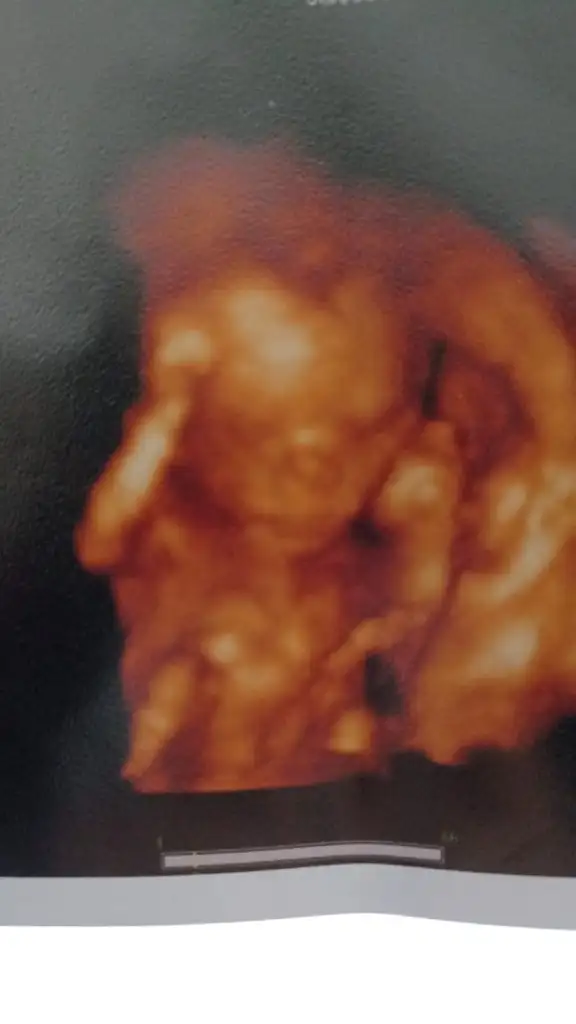

Oy maşallah ne de güzel çıkmış eva hanımBizim de bugün kontrolümüz vardı çok şükür bir sıkıntı görmedi doktorum 4 Mayıs ta ayrıntılı ultrason yapılacak gün verdi tetanoz aşısı ol 2 doz mutlaka dedi cinsiyetimiz belli oldu bir kızımız olacak teyzeleri ilk pozumuzu da verdik ekliyorumNewMamaa adımız da Eva olacak kısmetse

Amanın amanın maşallahBizim de bugün kontrolümüz vardı çok şükür bir sıkıntı görmedi doktorum 4 Mayıs ta ayrıntılı ultrason yapılacak gün verdi tetanoz aşısı ol 2 doz mutlaka dedi cinsiyetimiz belli oldu bir kızımız olacak teyzeleri ilk pozumuzu da verdik ekliyorumNewMamaa adımız da Eva olacak kısmetse

Maşallah Allah bağışlasın kaç haftalikken öğrendiniz cinsiyetini yavrunuzunBizim de bugün kontrolümüz vardı çok şükür bir sıkıntı görmedi doktorum 4 Mayıs ta ayrıntılı ultrason yapılacak gün verdi tetanoz aşısı ol 2 doz mutlaka dedi cinsiyetimiz belli oldu bir kızımız olacak teyzeleri ilk pozumuzu da verdik ekliyorumNewMamaa adımız da Eva olacak kısmetse

Bak baak poz da vermiş kız olduğu burdan belliBizim de bugün kontrolümüz vardı çok şükür bir sıkıntı görmedi doktorum 4 Mayıs ta ayrıntılı ultrason yapılacak gün verdi tetanoz aşısı ol 2 doz mutlaka dedi cinsiyetimiz belli oldu bir kızımız olacak teyzeleri ilk pozumuzu da verdik ekliyorumNewMamaa adımız da Eva olacak kısmetse